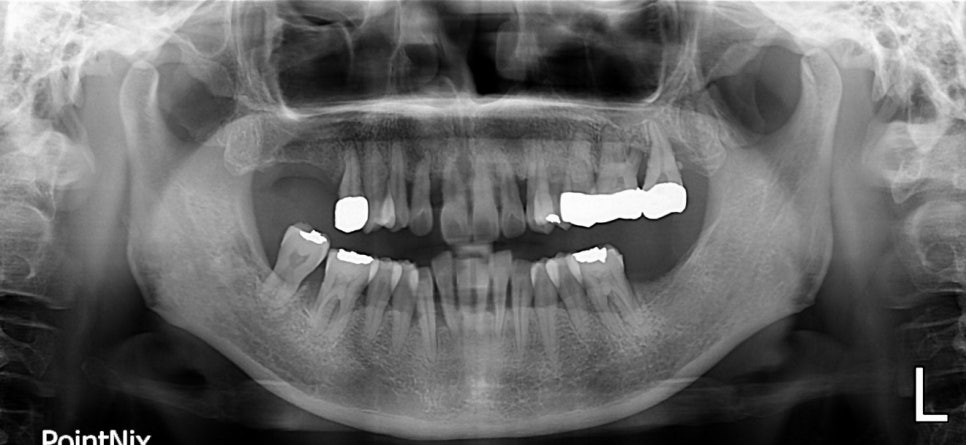

당뇨병 환자로 치주염을 앓고 있을 때의 X-RAY

당뇨질환을 가지고 계신 분 중 치주염을 앓고 계신 경우가 상당히 많습니다. 이러한 원인은 당뇨로 인해 면역기능이 약화되어 세균 감염의 위험이 일반 경우보다 높습니다. 당뇨병의 여러 합병증 중에 잇몸병은 6번째 정도 흔한 합병증이며,

치아를 감싸고 있는 잇몸과 뼈가 염증으로 인해 소실되는 질환으로 우리는 흔히 '풍치'라고 합니다.

양치시 제거되지 못한 세균들이 잇몸 주면에 쌓이는 치태(프라그)는 잇몸 염증을 일으키게 되고, 자각증상이 별로 없다가 심하게 진행된 후 발견되는 경우가 많아 결국 치아가 흔들려서 뽑게 되는 경우가 많습니다. ( 출처 : 서울아산병원 알기 쉬운 건강정보 중 )